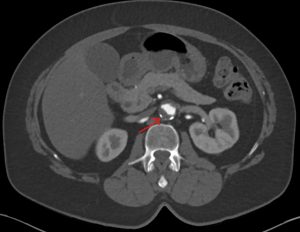

Mural thrombus

Mural thrombus in a small aortic aneurysm